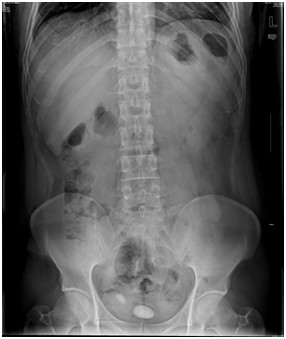

05卷-4.男,55歲,反復(fù)尿頻、尿痛、排尿困難半年(本題滿分2.00分)

A.膀胱癌

B.膀胱結(jié)石

C.前尿道結(jié)石

D.前列腺肥大

本題答案:B

【該題針對(duì)“ X線-泌尿系統(tǒng)陽(yáng)性結(jié)石 ”知識(shí)點(diǎn)進(jìn)行考核】